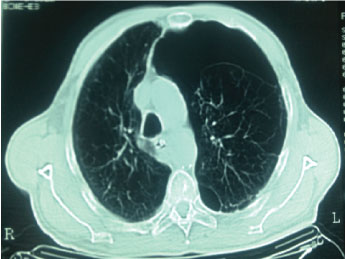

In the chest X-rays of the patient, one of them obtained in the emergency service and the other on admission to the Critical Care Unit, there is no arborization vascular in the lower left field, an image diagnosed as a giant bulla by the specialist in imaging, Pneumonologist and surgeon (Figure 1).

Figure 1: Chest X-rays of the patient, on admission to the Critical Care Unit. There is no arborization vascular in the lower left field, an image diagnosed as a giant bulla.